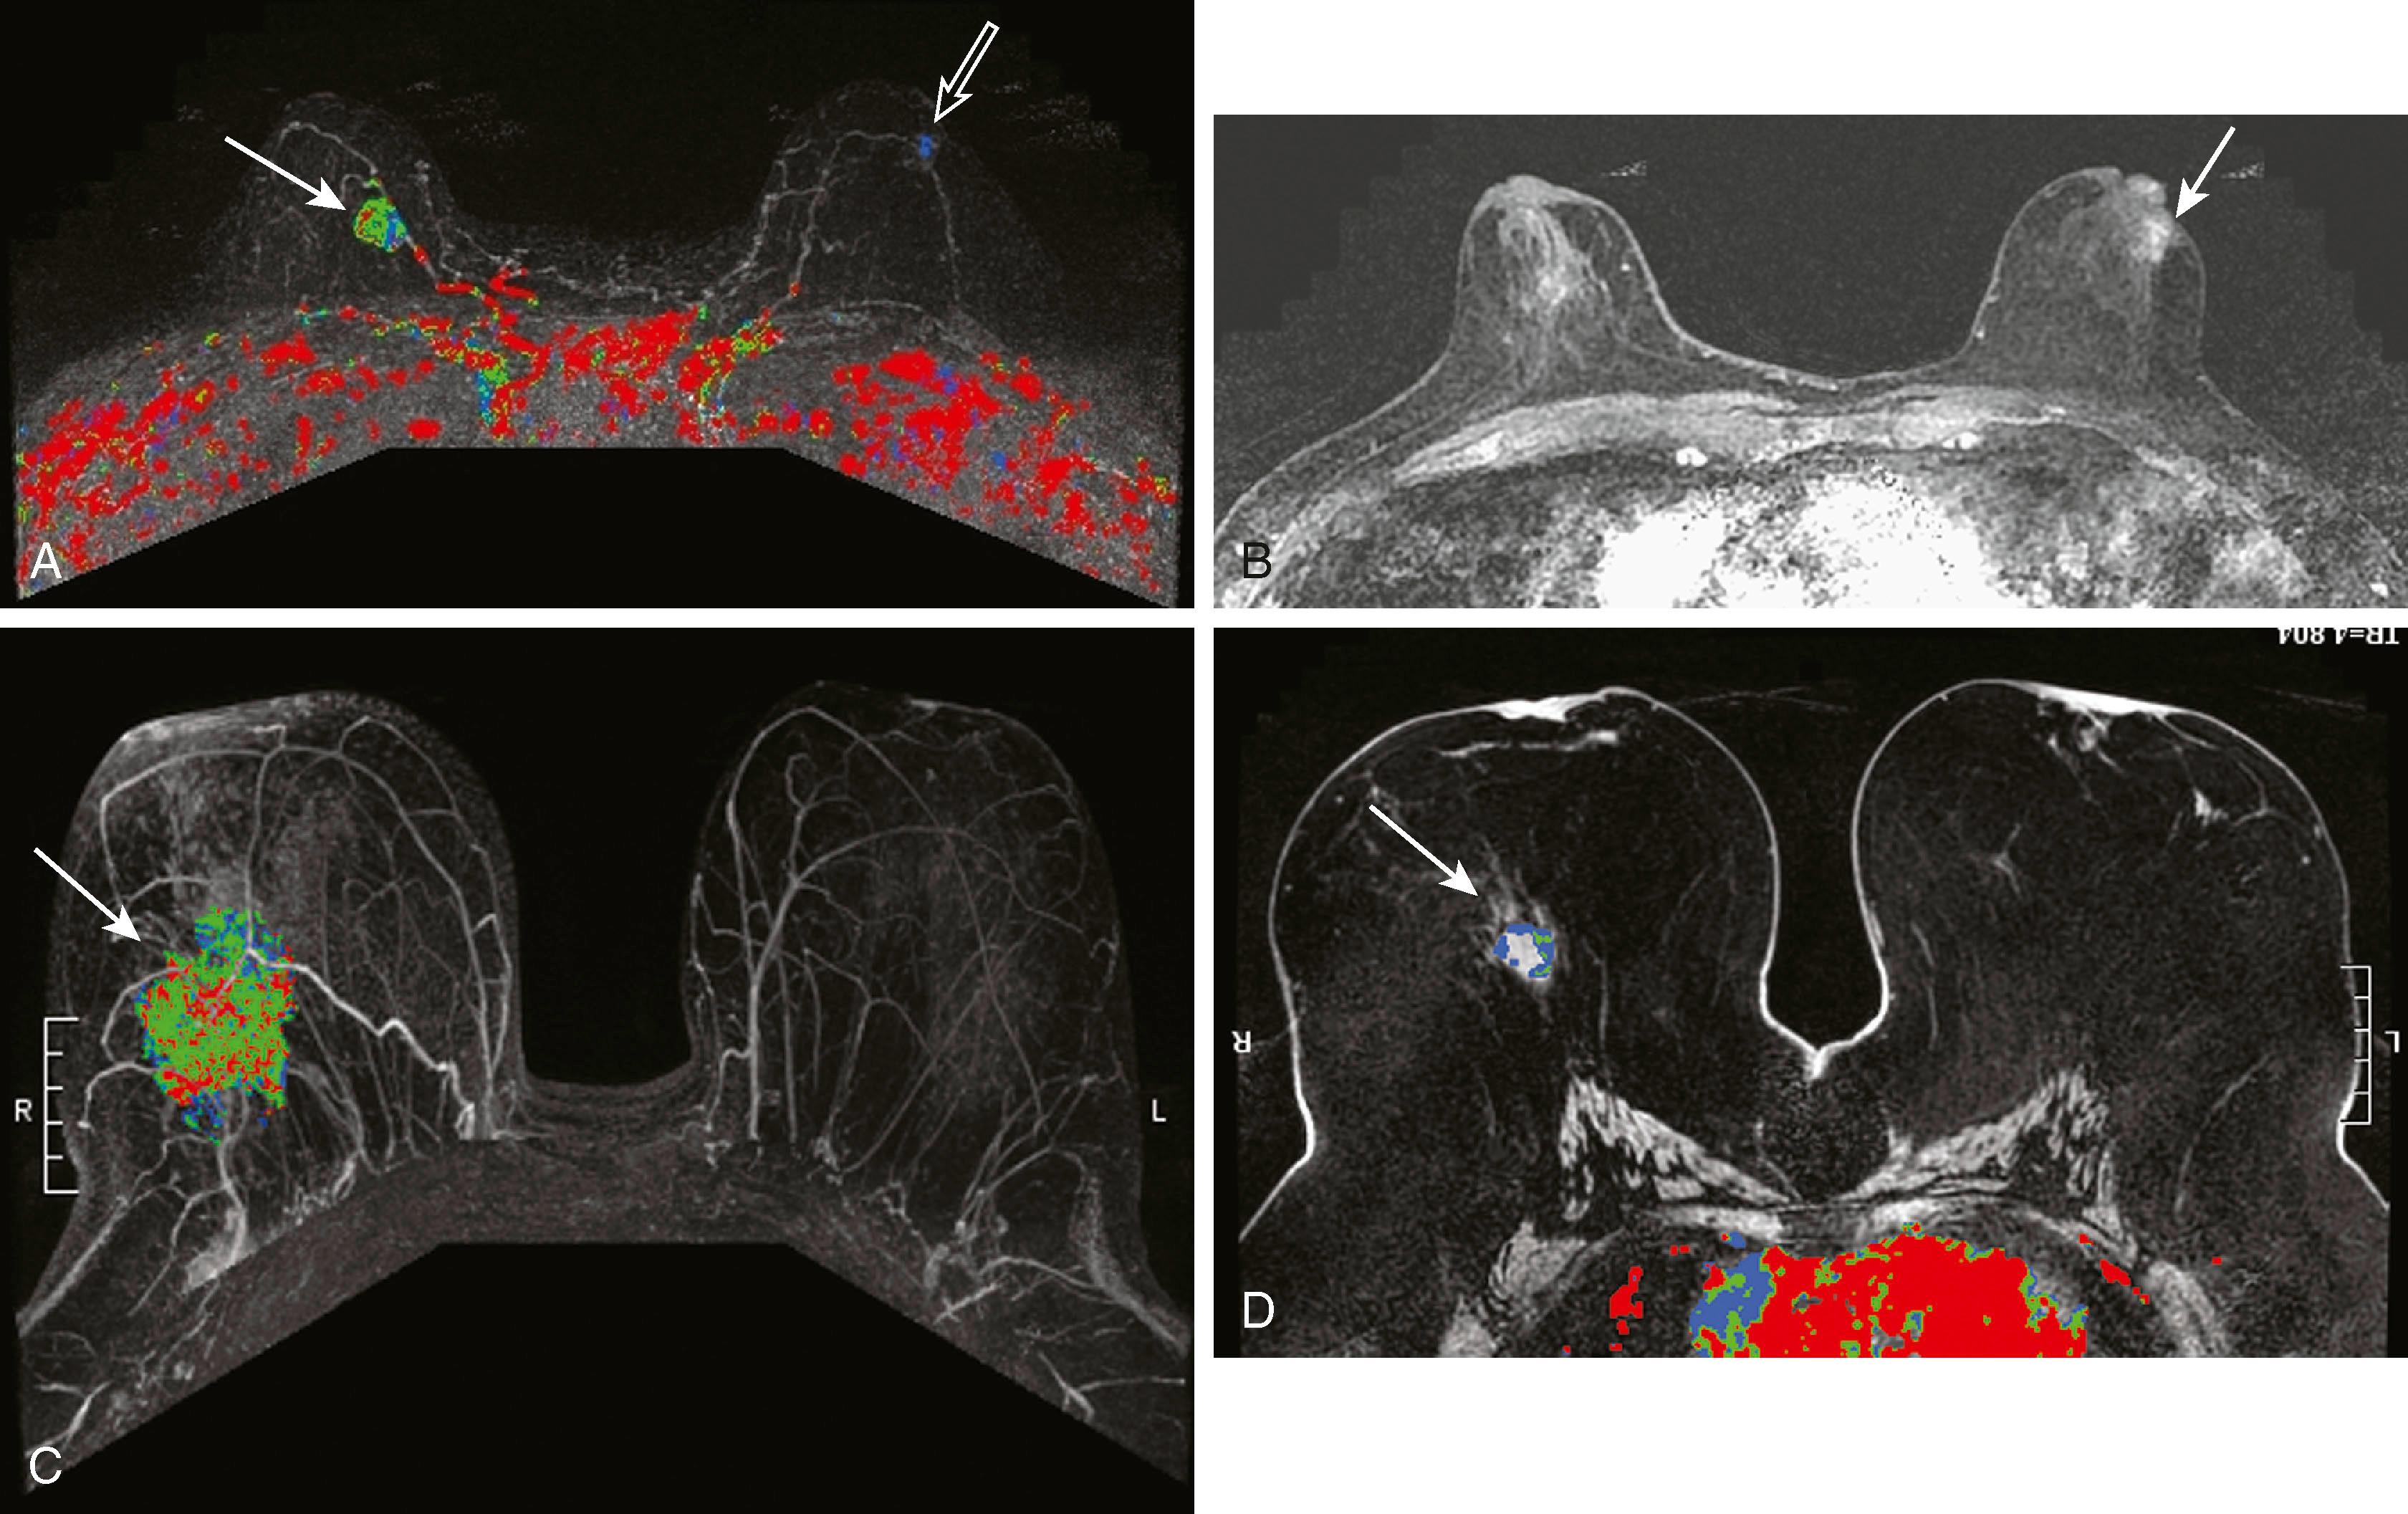

MRI detects breast disease by virtue of its ability, after the administration of a gadolinium-based contrast agent, to demonstrate neovascularity in tumors. Breast tumors, especially malignant ones, have more and larger vessels with higher permeability to contrast. In addition, there is an increase in the interstitial extravascular space of tumors. Typically, breast cancers enhance rapidly (within the first minute or so of contrast administration) followed by rapid washout over 10 to 15 minutes ( Fig. 8.22 ). This is the typical “kinetic signature” of cancer but, unfortunately, it is not absolute. There are a few cancers that demonstrate delayed enhancement with progressive accumulation of contrast and benign lesions, such as fibroadenomas, typically cellular, that enhance rapidly and wash out quickly ( Fig. 8.23 ). Therefore, when MRI-visible lesions are characterized, both the kinetic profile and the morphology must be considered. The morphological features that we have come to associate with breast cancer by most imaging techniques are indistinct borders, spiculation, and irregularity of shape.

Fig. 8.22, ( A and B ) Two examples of malignant lesions (arrows) , colored red by computer-aided detection (CAD). ( C ) The curve shows the typical “kinetic signature” of cancer, which is quick enhancement, followed by rapid washout. ( D ) Magnetic resonance imaging with CAD demonstrates a fibroadenoma within the right breast (arrow) , colored blue by CAD. ( E ) The washout curve for this fibroadenoma shows persistent accumulation of contrast.

Fig. 8.23, ( A ) Maximal intensity projection with computer-aided detection demonstrates a carcinoma within the right breast (solid arrow) showing a heterogeneous kinetic pattern of red, green, and blue, which is actually most typical for carcinoma. The left breast (open arrow) demonstrates a lesion showing benign washout; however, it is a carcinoma. ( B ) Although the kinetic profile is benign, the morphology of this lesion was malignant (arrow) . ( C ) Large invasive ductal carcinoma demonstrates a heterogeneous kinetic pattern (arrow) . ( D ) Carcinoma demonstrates a ring of predominantly blue enhancement (arrow) . Ring enhancement, however, is a malignant morphological feature.

Protocols to image breast cancer can vary, but the basic technique of breast MRI is to scan both breasts rapidly over time before and after the administration of an intravenous gadolinium contrast agent. Scanning is usually performed in the axial plane, but in some institutions, the sagittal plane is preferred. Because these scans result in very large data sets (a typical study will commonly include well over 1,000 images), computer algorithms that simplify viewing are helpful. The software that displays the kinetic features of the breast is referred to as CAD software. CAD assigns a color map to areas of blood flow, which is color coded depending on the speed with which the contrast exits the lesion. To demonstrate this, the breasts must be scanned multiple times in rapid succession (called multiphasic imaging ) over a short period, typically 10 to 12 minutes. Newer protocols are evaluating the efficacy of shortening the exam time by limiting the number of post contrast series obtained. If the contrast exits the lesion quickly, it is called a washout pattern and is usually colored red. This is most typical of malignant lesions and benign or malignant lymph nodes. If the contrast stays at the same concentration throughout the scan, it is called a plateau pattern and is often colored green. This pattern is indeterminate for malignancy. If the contrast enters the lesion and the concentration of contrast continues to increase, it is characterized as a persistent pattern and is typically colored blue. This pattern is most commonly seen with benign lesions such as fibroadenomas and other fibrocystic conditions.